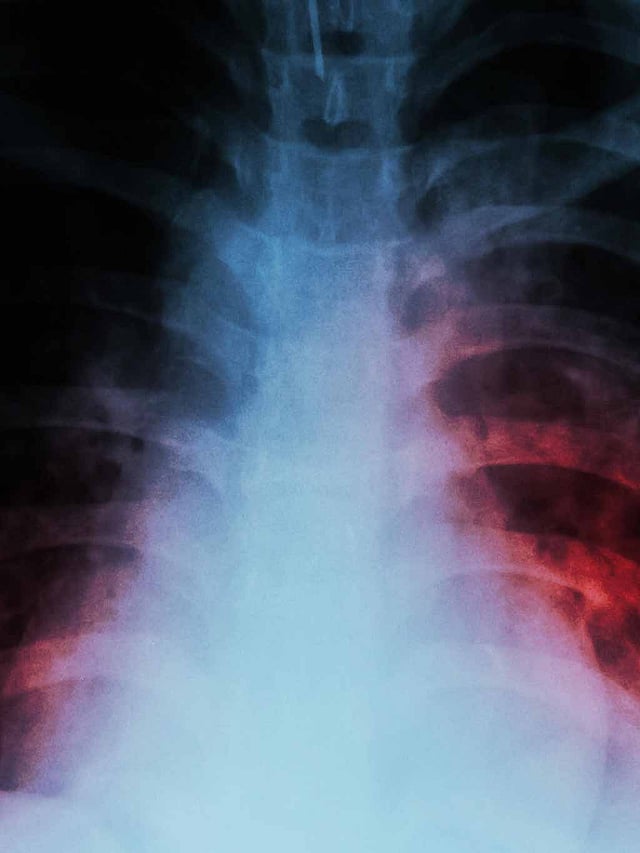

Salcit Technologies to Use AI For Detection of Tuberculosis

Salcit Technologies is exploring the use of Google's Health Acoustic Representations (HeAR) model to enhance early detection of tuberculosis.